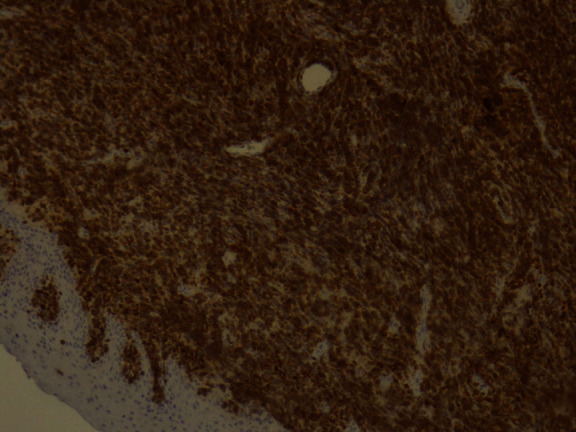

The tumor surface molecules were studied by immunophenotyping (Table 1) to clarify the nature of cancer and establish the appropriate treatment protocol. The positive Clusters of Differentiation (CD) were CDs 34, 45, 20, 79A, and 10 together with the marker MIB 1/Ki-67 (Figures 10–15).

CD20: weak positive.

Figure 14.

After recognizing the hematopoietic origin, the use of the marker CD20 was warranted because of the history of leukemia and the leukemic cell appearance at the cytology report. CD20 is negative or weakly positive in B-ALL and B lymphoblastic lymphoma and is used as screening for justifying that a tumor derives from B cell lineage since CD20 is negative in T-ALL and AML [23].

Furthermore, positivity for CD20 is considered as a good prognostic factor. This is because therapeutic anti-CD20 agents have been developed and are available as treatment regimes. The medications based on CD20 are rituximab, ibritumomab, and tositumomab which have been used in the successful treatment of both B-ALL and Burkitt leukemia and lymphoma [25].